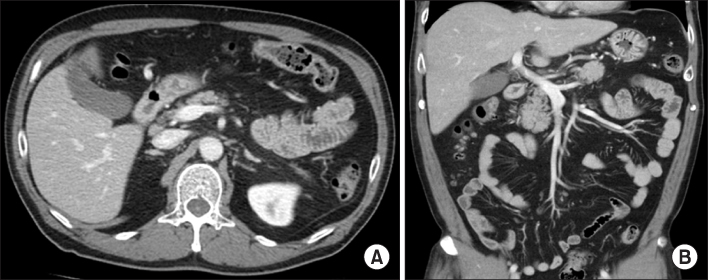

Fig. 1

Computed tomography (CT) findings on admission. (A) Axial CT image shows necrotic changes in the pancreatic tail, fluid collections in the peripancreatic space (arrowheads) and portal vein thrombosis (arrow). (B) Coronal CT image shows portal vein thrombosis extension to splenic vein (arrow).

Fig. 1 Computed tomography (CT) findings on admission. (A) Axial CT image shows necrotic changes in the pancreatic tail, fluid collections in the peripancreatic space (arrowheads) and portal vein thrombosis (arrow). (B) Coronal CT image shows portal vein thrombosis extension to splenic vein (arrow).